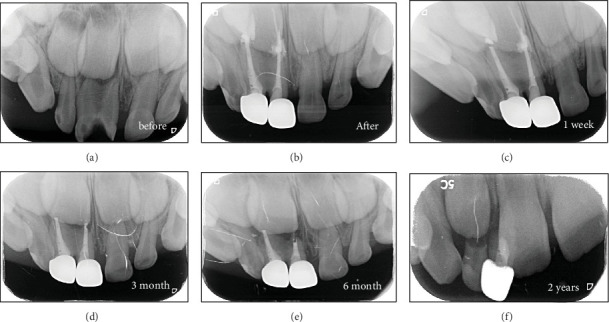

Fusion is a developmental dental anomaly that may affect both dentitions. The condition occurs during the developmental stage when two different tooth buds fuse. Depending on the degree of fusion, teeth may be diagnosed with fusion, gemination, or macrodontia. This defect is typically described as primary double teeth. The main clinical problems associated with primary double teeth include dental caries, crowding, occlusal discrepancies, and poor aesthetics. This report presents the clinical experience of managing 13 primary fused anterior teeth. The aim was to preserve and restore the decayed teeth while maintaining function and aesthetics. Treatment varied from the application of preventive measures to the separation of fused teeth. Clinical and radiographic diagnoses were used to determine the appropriate treatment plan. Decay removal was followed by restoration using either composite or zirconia crowns. Some teeth required pulp treatment before final restoration; therefore, pulpectomy was performed, and the canals were sealed with a calcium hydroxide and iodoform mix. Evaluation criteria included clinical success, gingival health, function, and aesthetic preservation. Follow-up periods ranged from 1 to 4 years. The follow-up of the presented cases demonstrated that the selected preventive, restorative, and surgical approaches successfully retained the affected teeth in a stable and healthy condition.